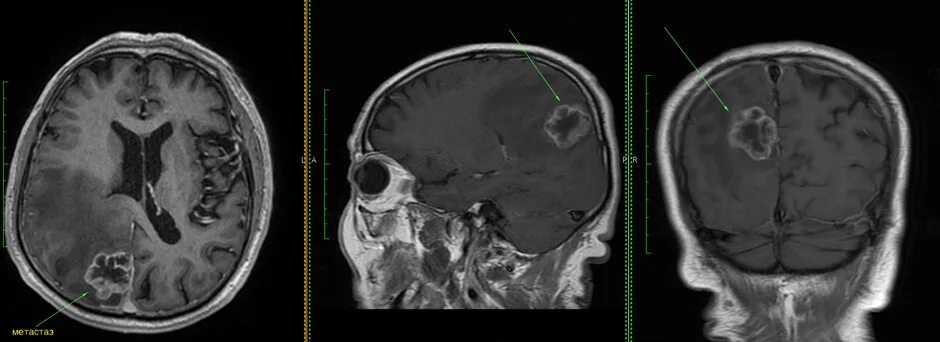

Метастазы головного мозга кт